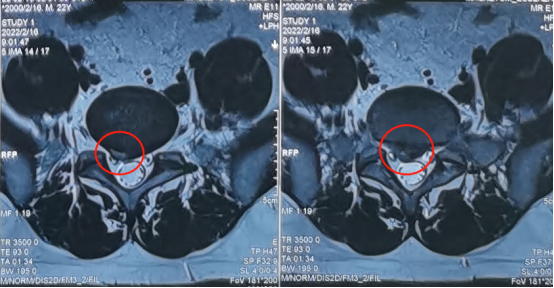

术前影像学资料

陕西冶金医院神经脊柱科的张少华主任、熊东主任接诊后,为小孙进行了详细的查体,并结合各项检查结果和影像学片子,发现他在腰5/骶1节段出现了比较严重的腰椎间盘突出,并造成较为严重的神经受压。

来到陕西冶金医院神经脊柱科后,由张少华主任、熊东主任接诊,经过各项检查后发现他在腰3/4、腰4/5、腰5/骶1都有不同程度的突出,尤其是在腰4/5突出非常严重。鉴于曹先生主要的症状表现和影像学等检查结合,判断腰4/5为主要责任节段,并建议尽快进行微创手术,给神经进行解压。